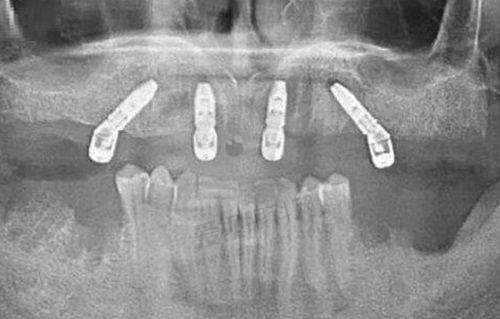

周军军 医生是东营严选口腔(叁十二洁牙齿科)的副主医师,其主要执业机构包含柏年严选(东营)医疗服务有限公司松鼠儿童口腔医院。他毕业于山东大学口腔医学校,是硕士学历,拥有超过18年的口腔医学从业经验,尤其在种植牙领域表现出色。他擅长处理缺牙、部分牙列缺损和全口牙列缺损等复杂情况,采用微创技术进行种植,能够减少患者的创伤和不适感,手术过程几乎微痛感,修复也比较快。此外,他还擅长即刻种植和全口/半口牙颌种植等技术,能够根据患者的具体需求制定合理的治疗计划。有这样专精的医生坐诊,患者的口腔问题能够得到更有效的解决。